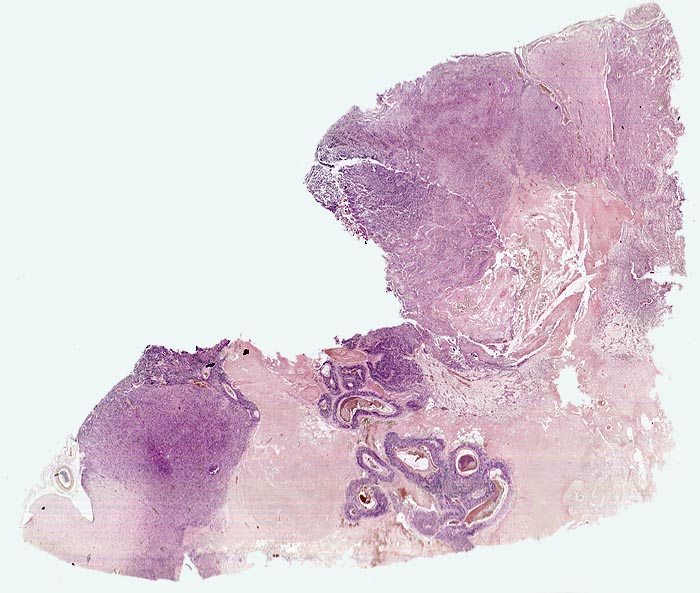

Morphologische Merkmale:

• Zellreicher Tumor mit sehr unscharfer Begrenzung zum normalen Hirnparenchym (rechts unten).

• Typische streifenförmige Nekrosen mit randständiger Palisadierung der Tumorzellen.

• Im Zentrum der Nekrose thrombosierte Gefässe umgeben von einem Saum vitaler Tumorzellen.

• Pathologische glomerulumartige zellreiche Gefässknäuel.

• Ausgeprägte Zellpolymorphie und Atypie.

• Mitosen.